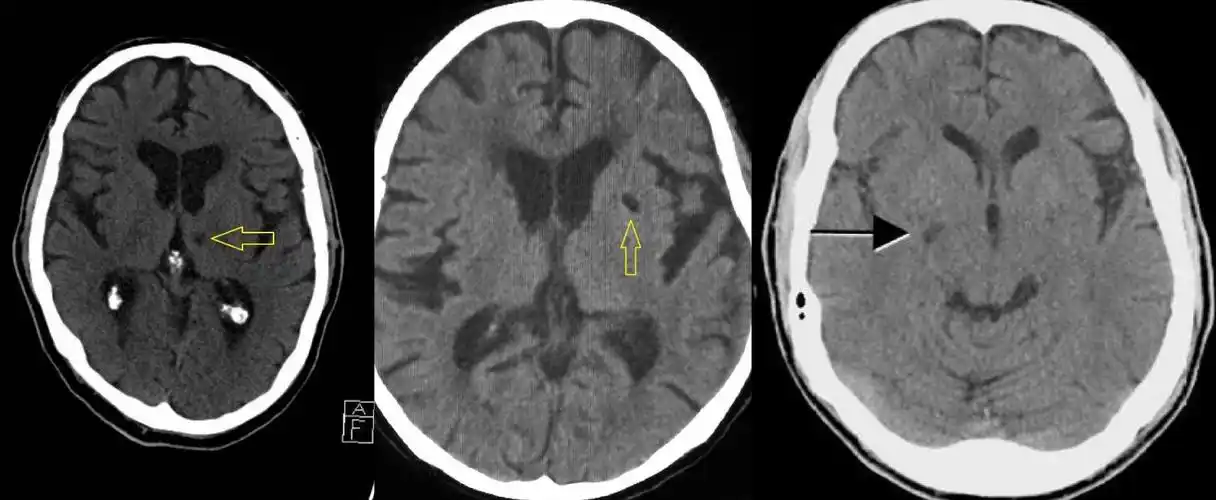

5大ct征象诊断脑梗死

汇总超早期脑梗死ct征象